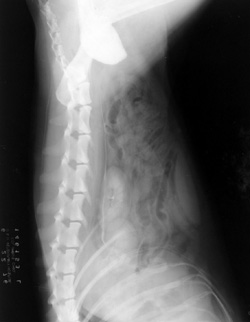

On this IVP, not the odd appearance of the right kidney. A knot from a lead rope was lying underneath the dog's body when the film was taken.